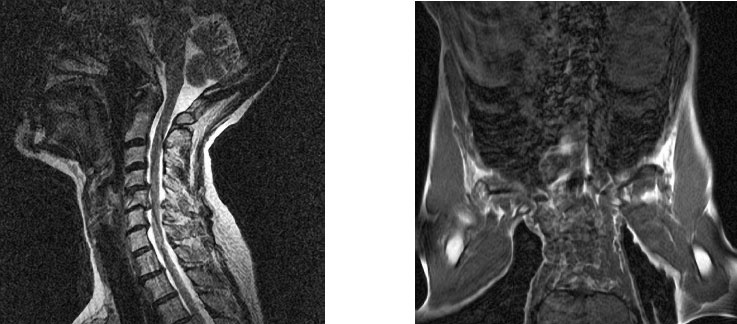

Рисунок 36. На левом снимке показано, почему ретролистез не позволяет выполнять стойку на голове. Даже в прямом положении V шейный позвонок угрожает целостности спинного мозга. Во время стойки на голове (справа) содержимое брюшной полости давит на перевернутые своды диафрагмы, усиливая ее сокращение при вдохе, что укрепляет все мышцы дыхательной системы и стимулирует кости и позвонки, к которым они крепятся.